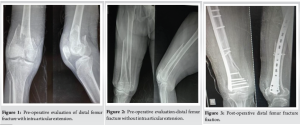

Forty-eight patients were included in this study. Closed, Open grade I injuries and polytrauma patients were included in this study. In our study patients were of age group between 21 and 70 years (Average age was 40.6 years). There was a male preponderance (5:1) in our study. The majority of the patients had a history of road traffic accidents or fall from height. In our study, we included both intraarticular and extraarticular fractures, among which 66.7% are intraarticular fractures (Fig. 1) and 33.3% are extraarticular fractures (Fig. 2). Both types of fractures are fixed with anatomical LCP (Fig. 3 and 4). In our study, there were 26 cases of closed injuries (54.2%) and 22 cases of open injuries (45.8%). In our study 38 (79.2%) patients were fixed as definitive treatment in the primary procedure and 10 (20.8%) patients were fixed as definitive treatment in the secondary procedure due to the presence of open injuries which was fixed with an external fixator in the primary procedure. In our study most common early complication was infection which was occurred in 16 patients (33.3%) in which 14 developed deep infection and 2 patients had superficial infection which was resolved within 10 days. Patients who had deep infections were treated with wound debridement before discharge. The average stay of hospitalization of our study was 18.8 days. The majority of the patients (58.3%) were mobilized from the knee joint with high sitting immediately after operative intervention rest all were given immobilisation splint for 4 weeks. All patients were discharged with non-weight-bearing. On long-term follow-up, 29.2% of patients (14 patients) had knee joint stiffness, 4 patients had malunion and 4 patients had delayed union. 2 patients had non-union on final follow-up. The average time of union in our study is 18.2 weeks. The majority of the fractures united between 15 and 20 weeks. In our study, 66.7% of patients (32) returned to their previous occupation while 12.5% of patients (6) had to change their occupation and 20.8% of patients (10) had unable to return their occupation. In our study, 32 patients had no complaints of pain, 8 had intermittent pain, 6 had pain with fatigue and 2 had pain with restricted function. In our study, only 2 patients had shortening >1.5 cm and 10 patients had fixed flexion deformity. The average degree of knee range of movement in our study was 100° (Fig. 5). 10 patients had <90° of range due to associated soft tissue injury and comminution at the fracture site. 66.7% (32) of our patients were able to walk without a limp and support on the final follow-up. 8 patients required some kind of support while walking. In our study, there were 50% satisfactory results (20.8% excellent, 29.2% good) and 50% unsatisfactory results (29.2% fair, 20.8% poor). In our study, out of a total of 48 patients, 26 (54.2%) patients had close fractures and 22 (45.8%) had open fractures (Gustillo-Anderson Gr-I type). Out of 26 (54.2%) close fractures, 8 patients had excellent results, 10 had good results, 6 had fair results, 2 had poor result at the final follow-up (Table 1). Out of 22 open fractures, 8 patients had poor results, 8 patients had fair result, 4 patients had good result, and 2 patients had excellent results.